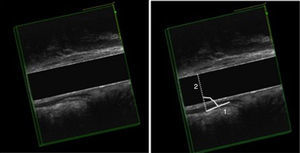

Anismo por EEAD: cierre del ángulo puborrectal más de un grado en la maniobra defecatoria, cuando se compara con el medido en reposo (fig. 1).

| 2.ª etapa | Reposo 35 s. Esfuerzo defecatorio máximo durante 20 s. Reposo 15 s | Músculo puborrectal y ángulo puborrectal | Relajación o contracción paradójica del haz puborrectal (anismo) |